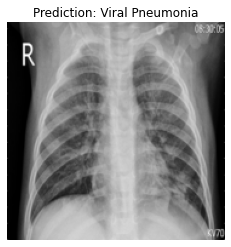

Currently, there is an urgent need for efficient tools to assess the diagnosis of COVID-19 patients. In this project, we propose a constructive solution for detecting and labeling infected tissues on CT lung images of such patients. To cut down false positives our model is trained on 4 types of lung CT images : COVID, Viral Pneumonia, Lung Opacity and normal images to get the best possible results with highest accuracy.

We built it using Tensorflow 2.x using Python. We have developed a Convolutional Neural Network model with an average accuracy of more than 85%.

We are proud that among the top 5 models, one of our models achieved 88.8% accuracy with very low loss.